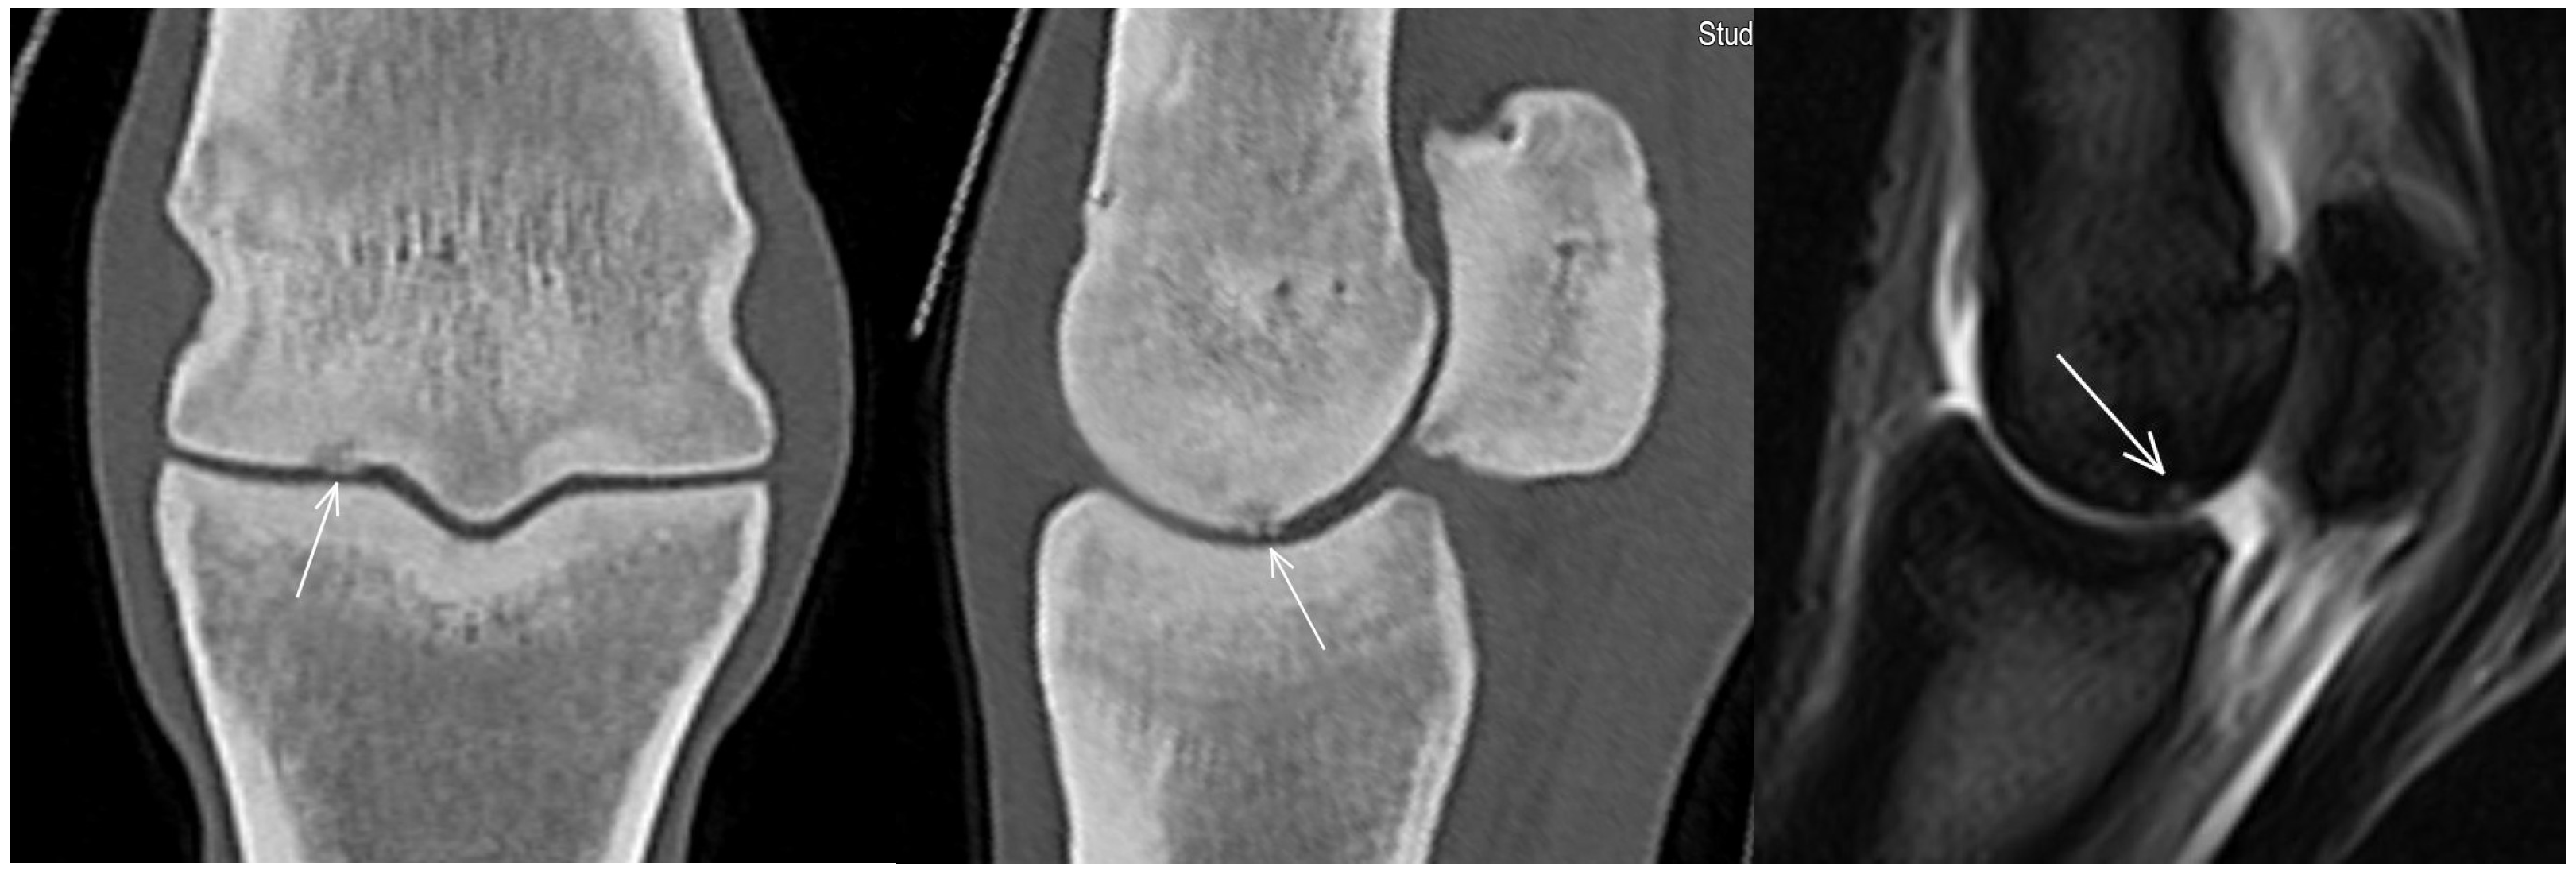

3.2. The Proximal Phalanx

| Proximal phalanx Sagittal groove | |||

| Subchondral bone thickening Dorsal/middle/palmar third Increased attenuation in the trabecular bone Hypoattenuating lesion in the subchondral bone Location | Subchondral bone thickening Dorsal/middle/palmar third Decreased signal intensity in the trabecular bone Increased signal intensity in the subchondral bone Location | Subchondral bone thickening Increased opacity in the trabecular bone Lucent lesion in the subchondral bone Location | |

- Lipreri, G.; Bladon, B.M.; Giorio, M.E.; Singer, E.R. Conservative versus surgical treatment of 21 sports horses with osseous trauma in the proximal phalangeal sagittal groove diagnosed by low-field MRI. Vet. Surg. 2018, 47, 908–915. [Google Scholar] [CrossRef] [PubMed]

- Lin, S.-T.; Foote, A.K.; Bolas, N.M.; Peter, V.G.; Pokora, R.; Patrick, H.; Sargan, D.R.; Murray, R.C. Three-dimensional imaging and histopathological features of third metacarpal/tarsal parasagittal groove and proximal phalanx sagittal groove fissures in Thoroughbred horses. Animals 2023, 13, 2912. [Google Scholar] [CrossRef] [PubMed]